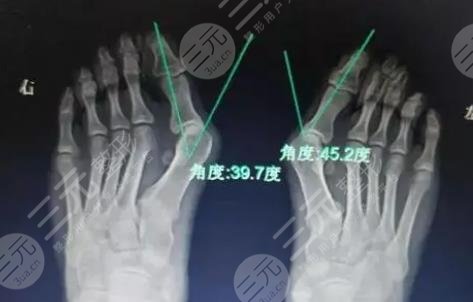

缓解大脚骨外翻的方式比较多,具体选择哪一种方法需要根据每个人的病情去评估。在选择方式之前,要根据求美者的症状,通过身体的检查和X线来综合去判断,不可以盲目的去选择,因此一定要到正规的医院,请经验丰富的医生去帮助选择和缓解。在缓解之后也要定期进行康复训练,避免一些不良反应出现。